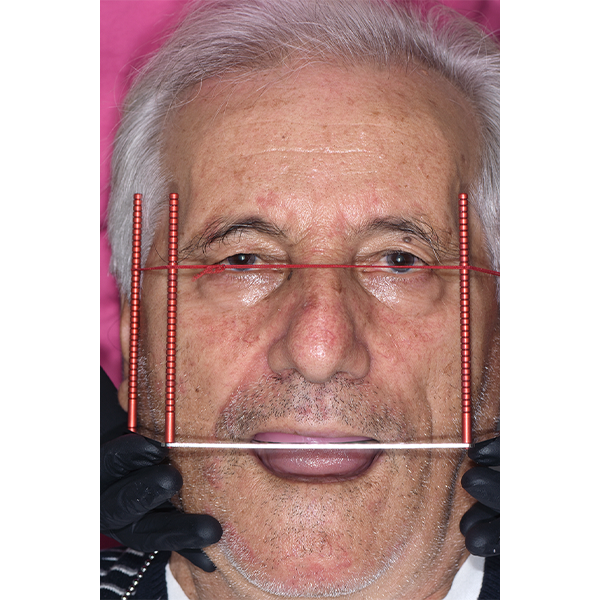

Après la mise en moufle et l'ébouillantage, les dents ont été repositionnées, conditionnées et des caractérisations blanchâtres, pourpres, orange clair, bleues et roses ont d'abord été réalisées au niveau du le bouclier labial. La base a ensuite été incrustée de résines pour prothèses de couleurs orange-rouge, rouge foncé, rouge clair, rose et rose foncé, et tous les polymères à chaud ont été pressés en une seule fois. Après le stockage sous pression, les prothèses finies ont été démouflées, finies et polies. La stratification anatomique tridimensionnelle de VITAPAN EXCELL en masse d'émail, de collet et de dentine avait un aspect absolument naturel dans l'anatomie muco-gingivale reproduite de la base prothétique. Le patient a pu s'habituer rapidement à sa nouvelle prothèse, notamment grâce à l'effet esthétique réussi. Après une courte phase d'adaptation et des corrections minimes dans l'environnement biodynamique, il s'est très bien débrouillé avec sa première restauration prothétique amovible complète et en était pleinement satisfait.